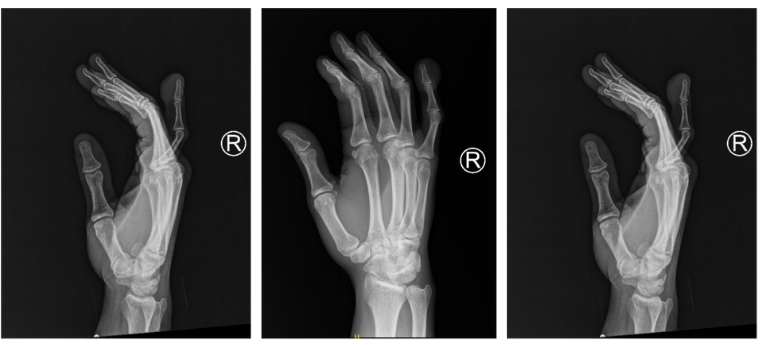

Radiographs of the right hand demonstrated a soft tissue mass along the ulnar aspect of the right little finger distal phalanx and preservation of distal interphalangeal joint space without cortical destruction or internal calcific density (Figure 2). Due to the patient’s limited hand function and the potential of malignant degeneration of the mass, a surgical procedure was recommended to remove the mass. After the benefits and risks of surgery were explained, the patient wished to proceed with the procedure.